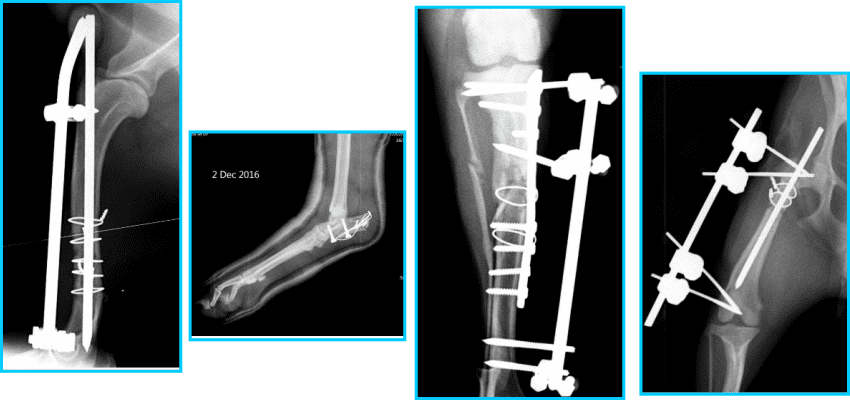

Để chẩn đoán chính xác tình trạng gãy xương, bác sĩ sẽ chỉ định thực hiện hình ảnh học, chủ yếu là X-quang. Kỹ thuật X-quang giúp phát hiện những gãy xương mà mắt thường không thể nhìn thấy. Nếu cần thiết, bác sĩ có thể sử dụng thêm các kỹ thuật hình ảnh khác như siêu âm hoặc chụp CT để thu thập thông tin chi tiết hơn về tình trạng xương và mô xung quanh. Từ đó, lược đồ điều trị sẽ được lên kế hoạch dựa trên kết quả chẩn đoán.

Gãy xương ở chó mèo là một tình trạng phổ biến, và việc điều trị thường yêu cầu các phương pháp phẫu thuật khác nhau để đảm bảo hồi phục tốt nhất cho thú cưng. Tại Phòng Khám Thú Y Dr.Vet, chúng tôi áp dụng một số phương pháp phẫu thuật hiện đại và hiệu quả để điều trị gãy xương, bao gồm nội soi, cố định xương bằng nẹp, vít, và những phương pháp khác.

Cố định xương bằng nẹp và vít là một trong những phương pháp truyền thống hơn. Kỹ thuật này bao gồm việc sử dụng các thiết bị cố định để giữ cho các mảnh xương trong vị trí chính xác. Phương pháp này có ưu điểm là sự ổn định cao và khả năng phục hồi mạnh mẽ, nhưng nhược điểm là cần một thời gian hồi phục lâu hơn và có nguy cơ nhiễm trùng tại vết mổ.